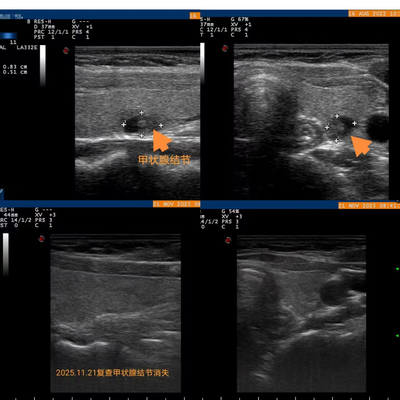

袁女士在五年前体检中发现甲状腺结节,后续复查中结节大小与形态均保持稳定,因而一直采取随访观察。2022年7月,她再次进行体检时,报告显示左叶结节被评定为4a类。尽管当时仍处于可观察范围,但随着时间推移,结节存在一定的病变风险。为从根本上杜绝隐患,袁女士决定积极寻求治疗。